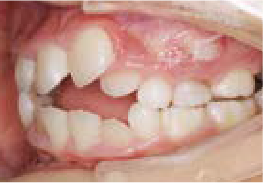

出っ歯

あごや骨格を正しく成長させる矯正治療

Aさん (矯正開始時:8歳)

Before

After

鼻がつまりやすく、口呼吸をしているために上あごが狭い状態でした。また上の前歯がかなり前へ傾いているため、お口をきちんと閉じていることができません。さらに、下の前歯もでこぼこしていました。

治療を終えて

装置によって上あごを拡大し、下あごを少し前へ成長させたことで、永久歯がきれいに並ぶスペースを確保しました。また、お口の機能が向上したことから鼻がよく通るようになり、口呼吸も改善され口も閉じやすくなったので顔の表情もよくなりました。

主訴・治療内容 下あごが後ろに下がり、出っ歯のようになっていることを心配して、無料相談に来院されました。

治療期間 2年半

費用 462,000円(税込)